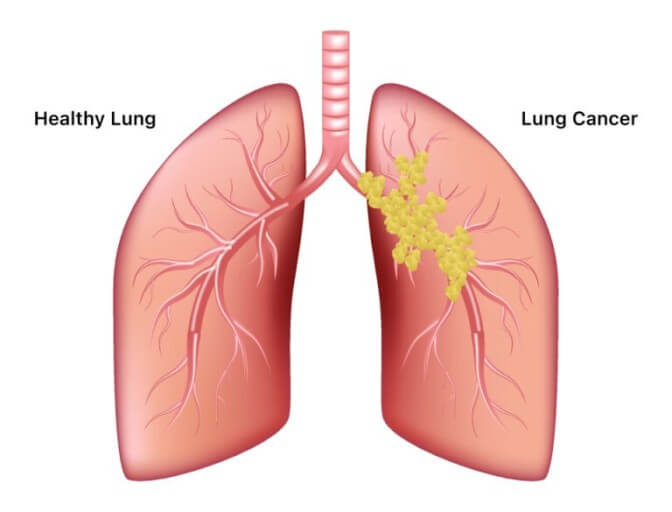

폐암 초기증상 : 폐암 4기 생존율은?

숨 쉬는 순간마다 위협하는 무서운 적, 폐암. 전체 암 사망 원인 1위를 차지하며, 진단 후 5년 내 사망률이 7~80%에 달하는 치명적인 질병입니다. 하지만 조기 발견 시 90%라는 놀라운 완치율을 기대